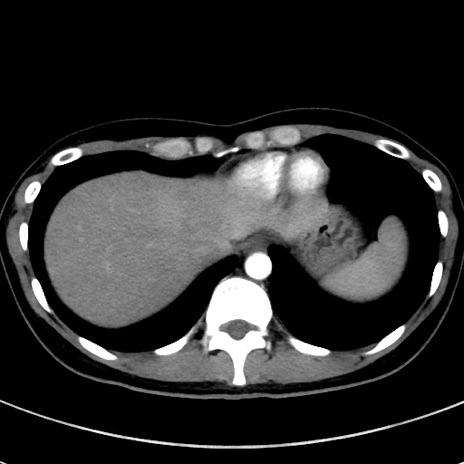

冠状断像